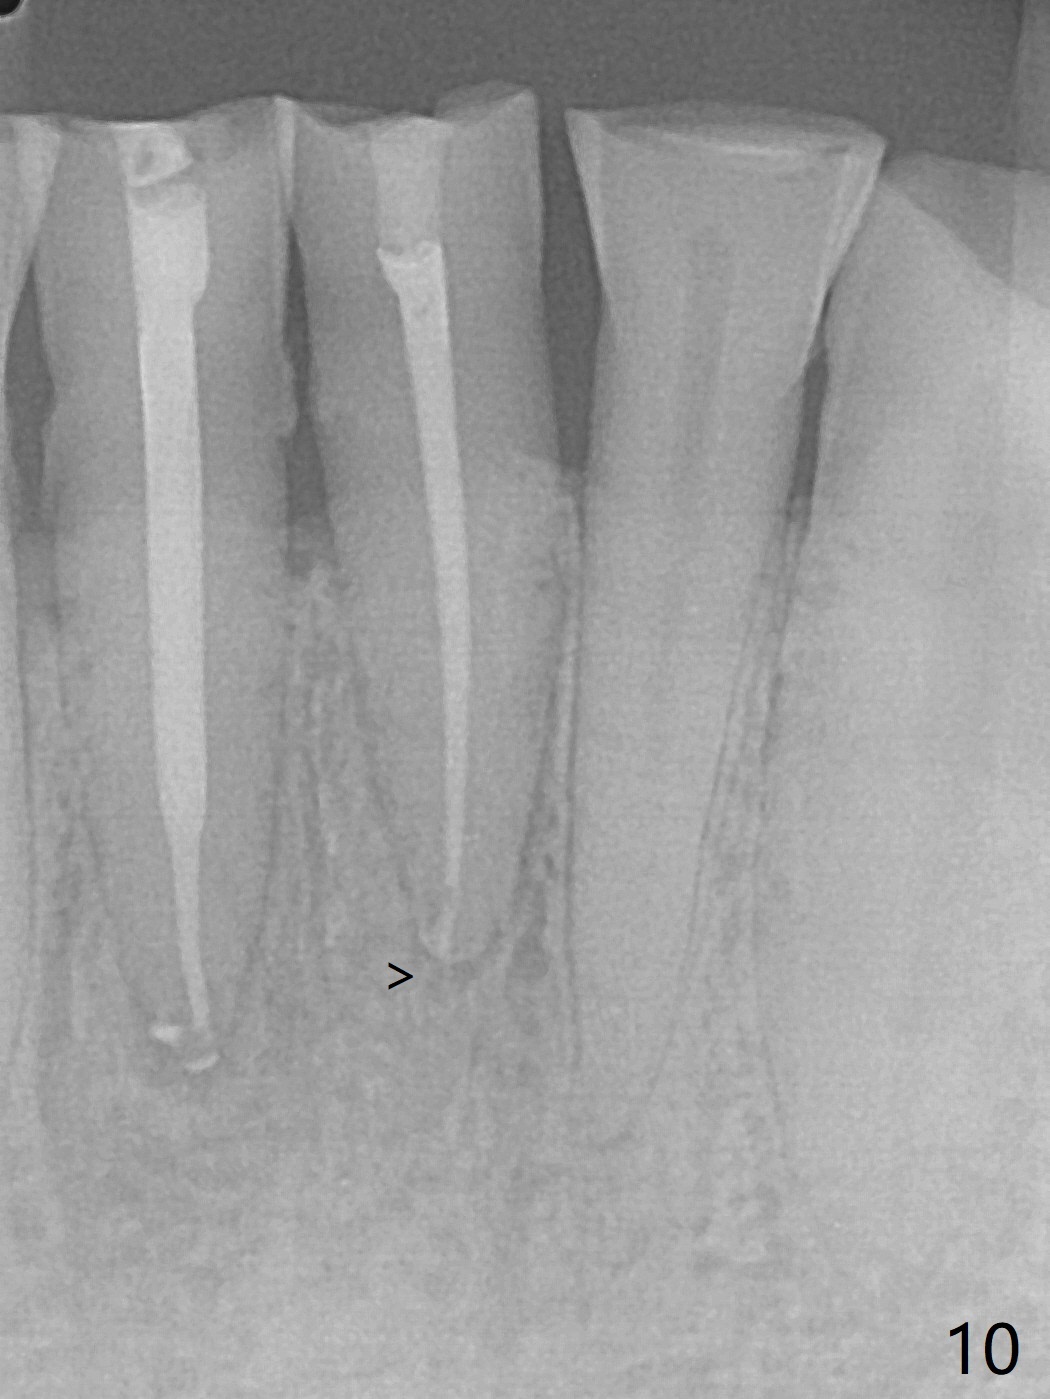

A 45-year-old man has had a chronic fistula associated with the tooth #25 (Fig.1). There is purulent discharge sometimes. After debridement with hand files #10-20 and rotary one 30/06, a master cone 30/.06 is inserted incompletely (Fig.2). After rotary files 30/.08 at 16.0 mm and 30/.10 at 15.0 mm and hand files 10-20 at 17 mm, the master cone is apparently inserted to the WL. With application of Endo Sequence Sealer (syringe), the master cone is reinserted (Fig.3). When the rubber dam is removed, the sealer is found to have expelled from the fistula. With an endo curette (Fig.5), the sealer is removed from the deepest portion of the sinus tract (apex of the tooth). What do you want to know the outcome of the supplementary surgical maneuver? The sealer is gone (Fig.6). The immediately supplementary treatment avoids a separate apicoectomy. No fistula is noted <2 weeks postop (Fig.7). The attrition is due to #8 and 9 veneers, fabricated 8 years earlier. The tooth #24 is symptomatic with loss of incisal composite nearly 4 years postop (Fig.8 <). After 30/.04 gutta percha (GP) try in (Fig.9), RCT is finished without accessory GP (Fig.10).